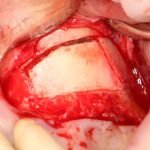

Кстати, обрати внимание на ширину альвеолярного гребня (левая картинка). Она чуть меньше 3 мм. Это объясняет, почему я засомневался в возможности установки имплантатов одновременно с остеопластикой. Понятно и без КЛКТ.